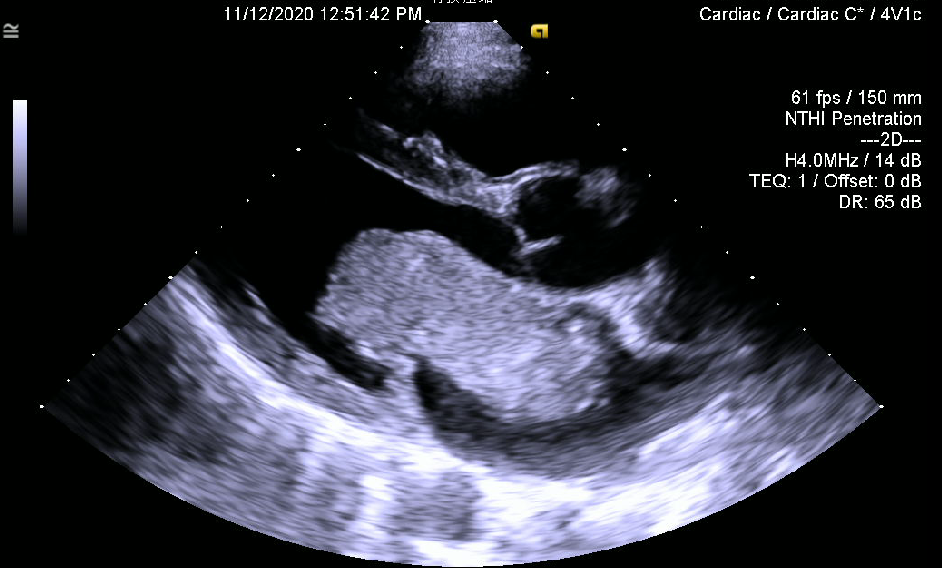

30多岁的患者小温就是这样的一位“心内炸弹携带者”。不久前,他出现了胸前区不适的症状,外院超声提示左房粘液瘤,瘤体长达9cm。瘤体在二尖瓣附近跳动导致二尖瓣功能受到影响,产生胸前区不适。

超声心动图显示的巨大肿物,从心房突入心室